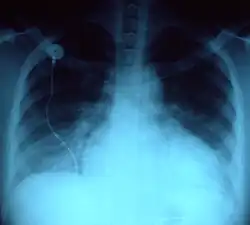

- powiększenie sylwetki serca (często nieobecne u pacjentów z dysfunkcją rozkurczową, na przykład w kardiomiopatii przerostowej)

- zmiany w krążeniu płucnym, przesięki